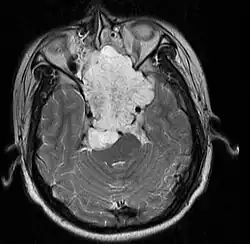

MRI of extensive clival chordoma in 17-year-old male patient, axial view. Tumor in the nasopharynx extending from nasal cavity to brainstem posteriorly is clearly visible. | |

Chordomas can arise from bone in the skull base and anywhere along the spine. The two most common locations are cranially at the clivus and in the sacrum at the bottom of the spine.[2] Very rarely, chordomas present outside of the skull base or spine; these are called extra axial chordomas.[3]